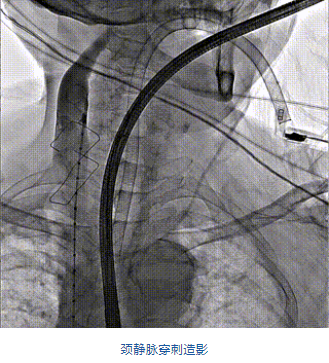

團(tuán)隊(duì)前期經(jīng)過多次討論,制定了周密的手術(shù)策略和預(yù)案。由于患者已是近九旬的超高齡老人,傳統(tǒng)外科開胸手術(shù)風(fēng)險(xiǎn)極高,純介入經(jīng)血管三尖瓣替換能夠明顯減少創(chuàng)傷。術(shù)中陳茂及馮沅教授結(jié)合體表定位在造影指示下精準(zhǔn)穿刺右側(cè)頸靜脈并預(yù)置兩把血管縫合器。成功建立經(jīng)皮血管入路后在食道超聲和DSA的引導(dǎo)下順利完成人工瓣膜植入,術(shù)后超聲和造影顯示人工三尖瓣同軸性良好,瓣架固定牢靠,無反流和瓣周漏,平均跨瓣壓差降為1mmHg。術(shù)畢收緊預(yù)置的血管縫合器縫線完成止血,縫合效果滿意,在手術(shù)室即刻拔除氣管插管。